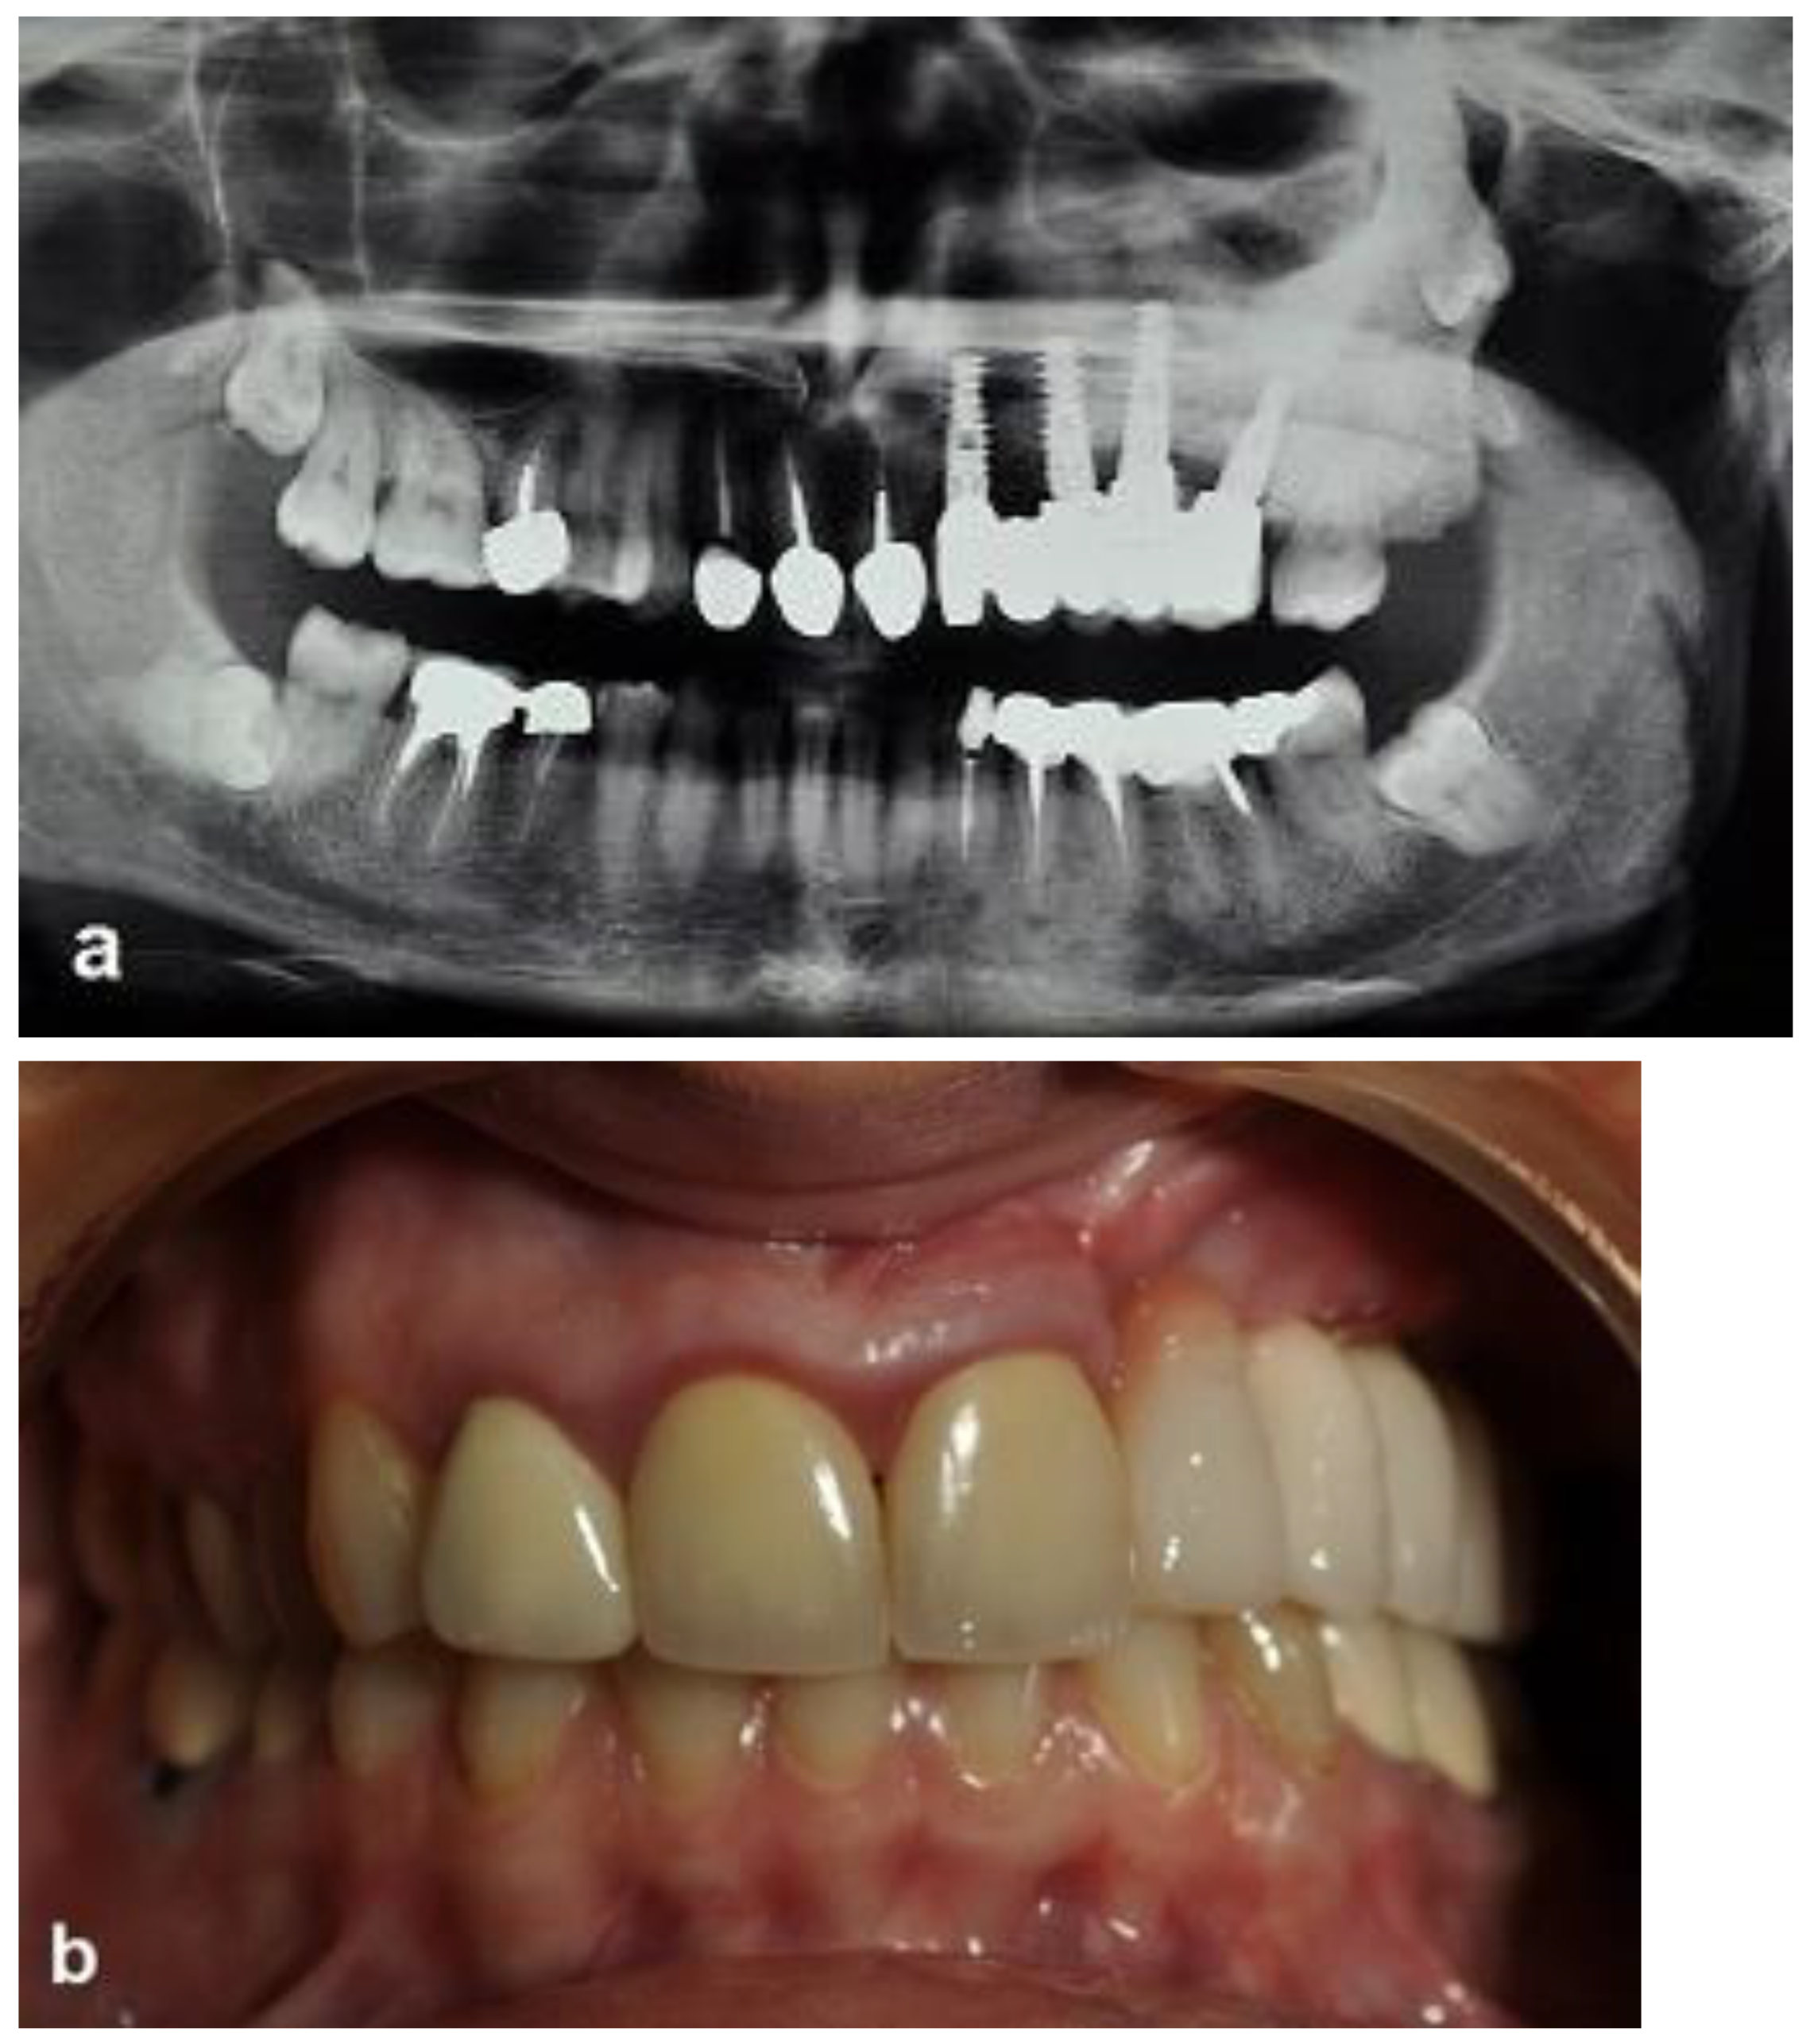

The second-stage surgical intervention was carried out 6 months later for dental implant placement. Four implants (SPI-Alpha Bio Tec., Modi'in-Maccabim-Re'ut, Israel), 3.75 diameter/13 mm length, were placed in the new bone site in the left posterior maxilla (Figure 6b). The dental implants were uncovered 4 months thereafter (Figure 7). An acrylic bridge was fitted over the implants as a temporary prosthesis (Figure 8), and this was replaced 12 months later by a fixed ceramic prosthesis (Figure 9a,b). The patient was then followed over 7 years.

First surgery: Healing at the 4 weeks follow-up visit after the surgery was uneventful (Figure 5a,b). During dental implant placement surgery that was carried out six months after the first surgery, a good bone quality was observed with normal bleeding (Figure 6a). All implants were clinically and radiographically successfully osseointegrated when exposed 4 months later (Figure 7). The final rehabilitation after one year, and throughout the long period of the follow-up, provides satisfactory esthetic and functional outcomes (Figure 10a,b). There were no obvious changes in the lesion dimensions after 7 years (Figure 10c).

Figure 9. Ceramic-implant-supported fixed prosthesis one year after implant placement shows implant osseointegration and good aesthetics. (a) Radiographic view. (b) Clinical view.